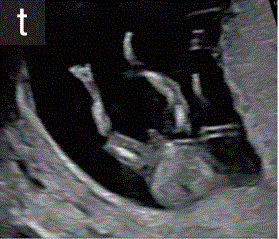

9 四肢

9.1 在11+0~14+0周超声检查中,应注意上肢和下肢三段的存在和双脚的存在和正常方向(图2t和2u)。

图2 11+0至14+0周时,可作为详细胎儿超声检查的一部分获得的解剖图。

(t)双下肢冠状面图,上肢、小腿、足三节段清晰可见。

(u)双侧上肢切面,上臂、下臂、手三节段清晰可见。妊娠早期的胎儿通常表现为张开的手,这可能有助于评估胎儿的手和手指。